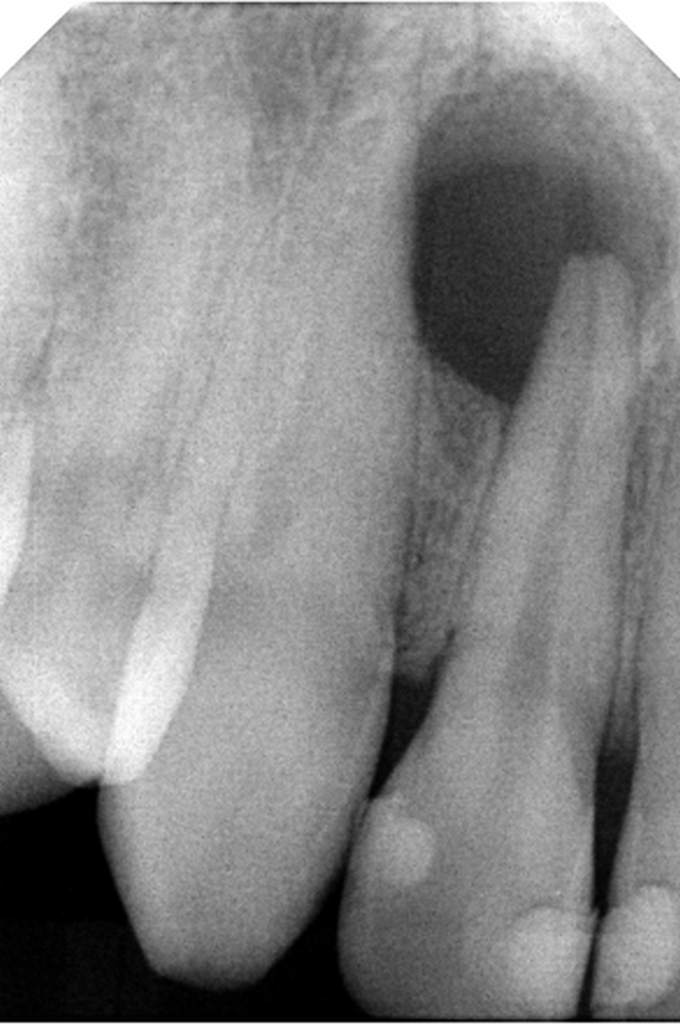

Αρχική εικόνα δοντιού

Εικόνα δοντιού μετά από επανάληψη θεραπείας

Η επανάληψη μιας ενδοδοντικής θεραπείας δεν σημαίνει και τη διάσωση τελικά του δοντιού. Η δυναμικότητα των παθογόνων αναερόβιων μικροβίων που έχουν αναπτυχθεί στο σύστημα των ριζικών σωλήνων με την συνεπακόλουθη καταστροφή των περιακρορριζικών ιστών καθιστά πολλές φορές αδύνατη τη διατήρηση του δοντιού, ακόμη και με τον συνδυασμό της μικροχειρουργικής ενδοδοντίας.

Τελική εικόνα δοντιού μετά από θεραπεία